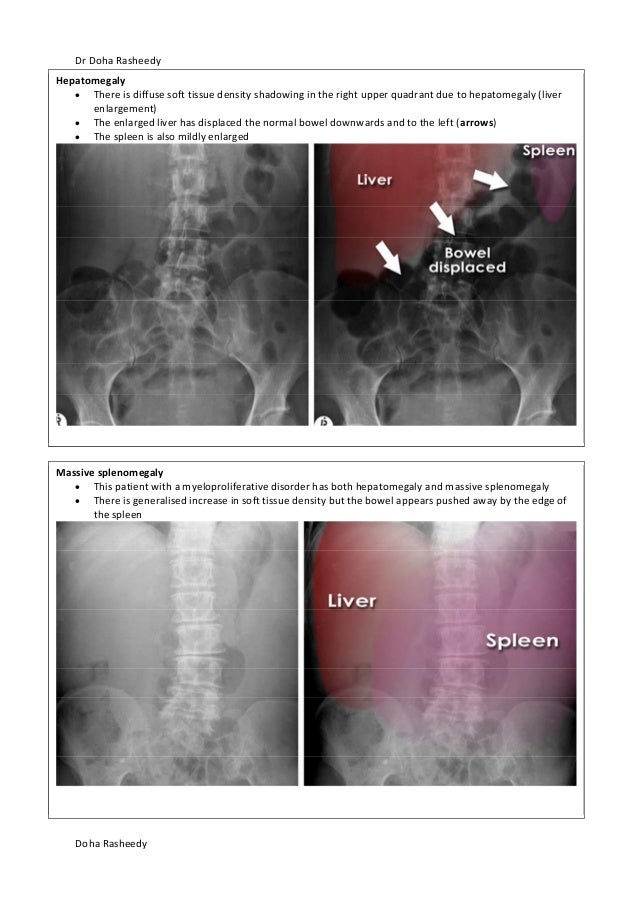

Extends to the hemidiaphragm; Although ultrasound and CT are more informative means of imaging the solid organs of the abdomen, occasionally you will see evidence of enlarged organs on an abdominal Xray Hepatomegaly Hover on/off image to show/hide findingsTalk to our Chatbot to narrow down your search

Psoas muscle symmetrical triangles either side of the lumbar spine Hepatomegaly can represent intrinsic liver disease or may be the presenting physical finding of a generalized disorder Early diagnosis and treatment of children who have liver disease is important because specific treatments are available for some diseases that can prevent disease progression or hepatic failureHepatomegaly is another word to describe this problem If both the liver and spleen are enlarged, it is called hepatosplenomegaly Abdominal xray;

Hepatomegaly is the condition of having an enlarged liver It is a nonspecific medical sign having many causes, which can broadly be broken down into infection, hepatic tumours, or metabolic disorder Often, hepatomegaly will present as an abdominal mass Depending on the cause, it may sometimes present along with jaundiceHepatomegaly (abdominal xray) Case contributed by Dr Jeremy Jones Diagnosis probable Diagnosis probable From the case Hepatomegaly (abdominal xray) Xray Loading Stack 0 images remainingSplenomegaly is a subjective radiograph finding as there are no reliable objective criteria;